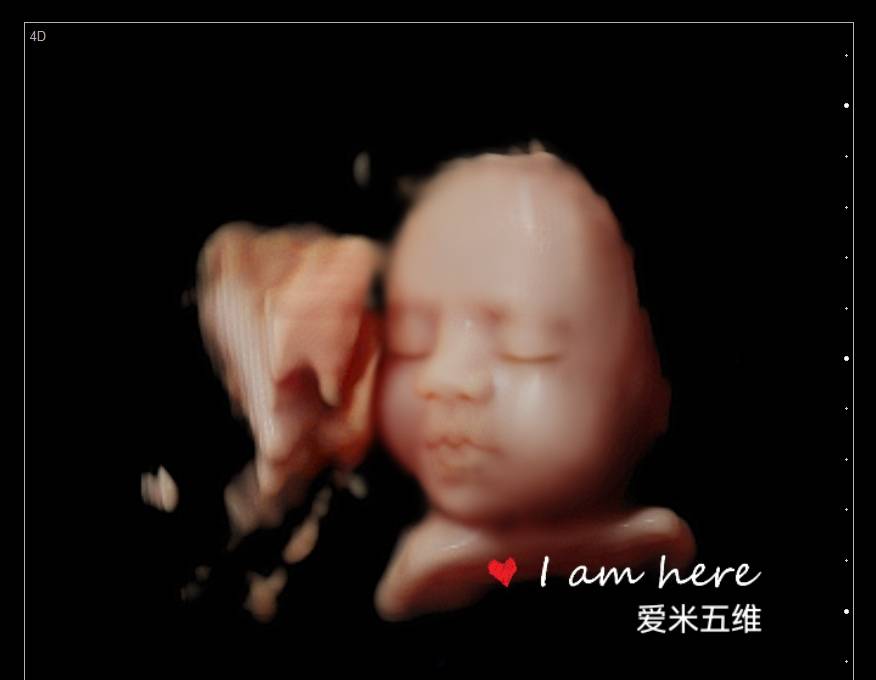

第一次五维看到了宝宝,好可爱,看的非常清楚,打印出来的照片也很清晰,第一次看到宝宝在肚子里的样子真的很激动,服务特别亲切,拍个五维还是很值得的

爱米孕婴摄影有着8年的拍摄历史,经验丰富、专业技术高超、并引进最新技术设备、呈现最完美影像照片,我们秉承着以客户满意为宗旨、资深影像师为您一对一的服务,宝妈可通过大屏幕清晰看到宝宝的各种动作及表情,让您感受与宝宝初次见面的激动,留下珍贵的瞬间!